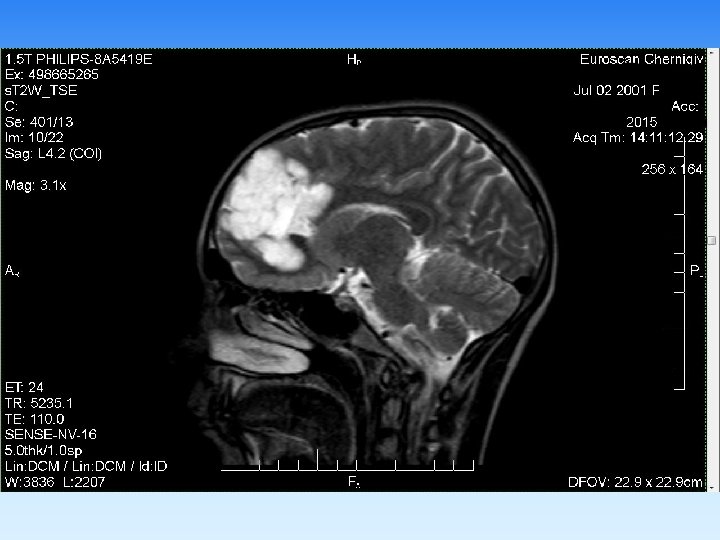

Примеры визуализаций

Имеющийся у нас набор катушек томографа PHILIPS Ahieva позволяет визуализировать с высоким качеством: § головной мозг (в т. ч. аномалии гипофиза, с применением контрастирования); § артерии и вены головного мозга; § орбиты и зрительные нервы; § все отделы позвоночного столба; § тазобедренный, коленный, плечевой, локтевой, височнонижнечелюстной, суставы; § лучезапястный сустав , запястно-пястный отделы кисти, стопы и голеностопные суставы; § почки и надпочечники; § печень, поджелудочную железу, селезенку; § предстательную железу, яички, мочевой пузырь, матку, яичники: § мягкие ткани тела.

§ В неврологической практике МРТ позволяет диагностировать аномалии развития, воспалительные, дисциркуляторные, неопластические процессы головного и спинного мозга, а также его оболочек. Кроме того, незаменимым метод является в диагностике патологии межпозвонковых дисков, паравертебральных мягких тканей, а также в скрининговой диагностике патологии сосудов головы и шеи. § В ортопедии МРТ показано при любой патологии гиалинового хряща, внутрисуставных связок, менисков, ротаторной манжеты плечевого сустава, синовиальных складок, что позволяет достоверно диагностировать их разрывы, отек, инфильтрацию. § При исследовании брюшной полости МРТ позволяет диагностировать заболевания печени, желчевыводящих протоков (режим холангиографии без применения контраста обеспечивает визуализацию холедоха, вирсунгова протока на всем протяжении), поджелудочной железы, селезенки, надпочечников, лимфатических узлов брюшной полости. § Широко используется МРТ в гинекологии и урологии, в маммологии метод позволяет диагностировать объемные процессы и их распространенность.